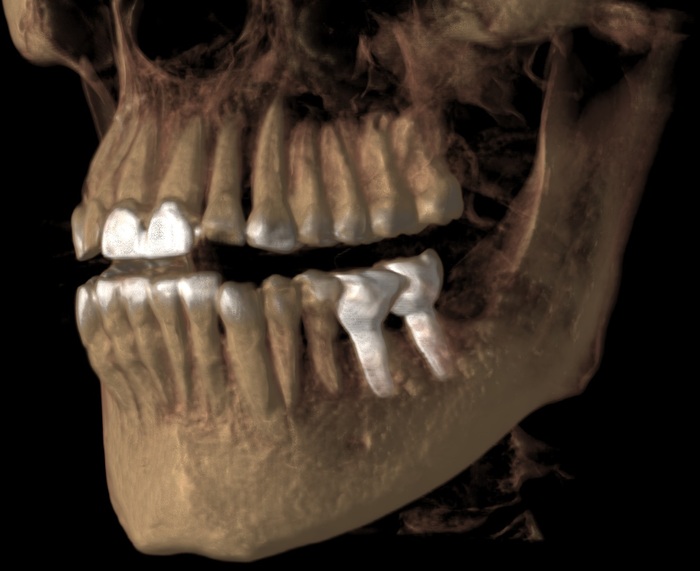

Прикус:

За эти годы ситуация усугубилась, стираемость зубов прогрессировала.

Вот как выглядели зубы в 2018 году:

А это через каких-то 3 года, 2021:

Обратите внимание, как сильно стерлась верхняя «двойка» и нижний клык:

Ниже ситуация от июня 2023: